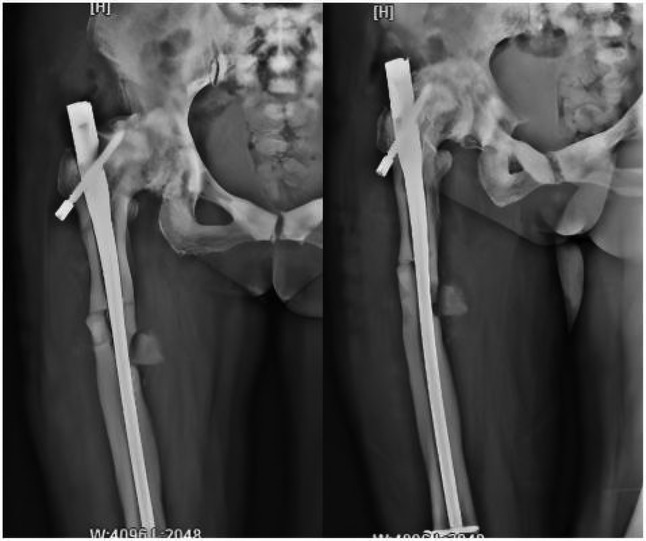

Following admission, the patient received symptomatic treatment including anti-inflammatory and analgesic therapy. Relevant laboratory tests and routine preoperative examinations revealed no significant contraindications for surgery. It was planned to perform a procedure to remove the internal fixation device from the right femoral trochanteric fracture and a closed reduction with intramedullary nail internal fixation for the right femoral fracture. The patient was placed in a supine position on a traction bed. An incision was made along the original surgical scar at the right hip, and the internal fixation device was removed. The apex of the right greater trochanter was then exposed. The needle insertion point was located at the anterior-medial one-third of the greater trochanter apex, slightly medial. The position of the guide wire was verified under fluoroscopy. The fracture was reduced on the traction bed, and the proximal end was dilated to 13 mm. and the distal end was dilated to 11 mm. After confirming the measurements, a 10 mm × 360 mm femoral intramedullary nail was placed. Under fluoroscopy, the fracture reduction was satisfactory. Two distal screws were locked in place using a targeting device, and the fracture ends were tapped and compressed. One proximal locking screw was inserted, and a 0 mm tail cap was installed. The surgery lasted 3.0 h, with an intraoperative blood loss of approximately 260 mL. On the second day postoperatively, a cephalometric and lateral x-ray examination of the femur was performed, with no abnormalities detected (Figure 2). The patient was discharged five days later, and was instructed to take anti-osteoporosis treatment after discharge, and isometric contraction of quadriceps femoris and ankle pump exercise were performed in bed 1–2 weeks after operation. 2–6 weeks after operation, straight leg lifting training, hip joint mobility training and partial weight-bearing exercise with walker were carried out; Six weeks after the operation, the patient changed to walking with one leg to carry out daily life training. One year after the operation, the x-ray examination showed that the fracture of femoral cadres healed well (Figure 3). During a follow-up period of over three years, the patient exhibited no significant neurological or motor dysfunction and no other complications were observed. The quality of life of patients has been greatly improved.

Figure 2. Postoperative x-ray images taken on the first day show that the intramedullary nail device is securely in place, and bone fragments are visible at the fracture site.